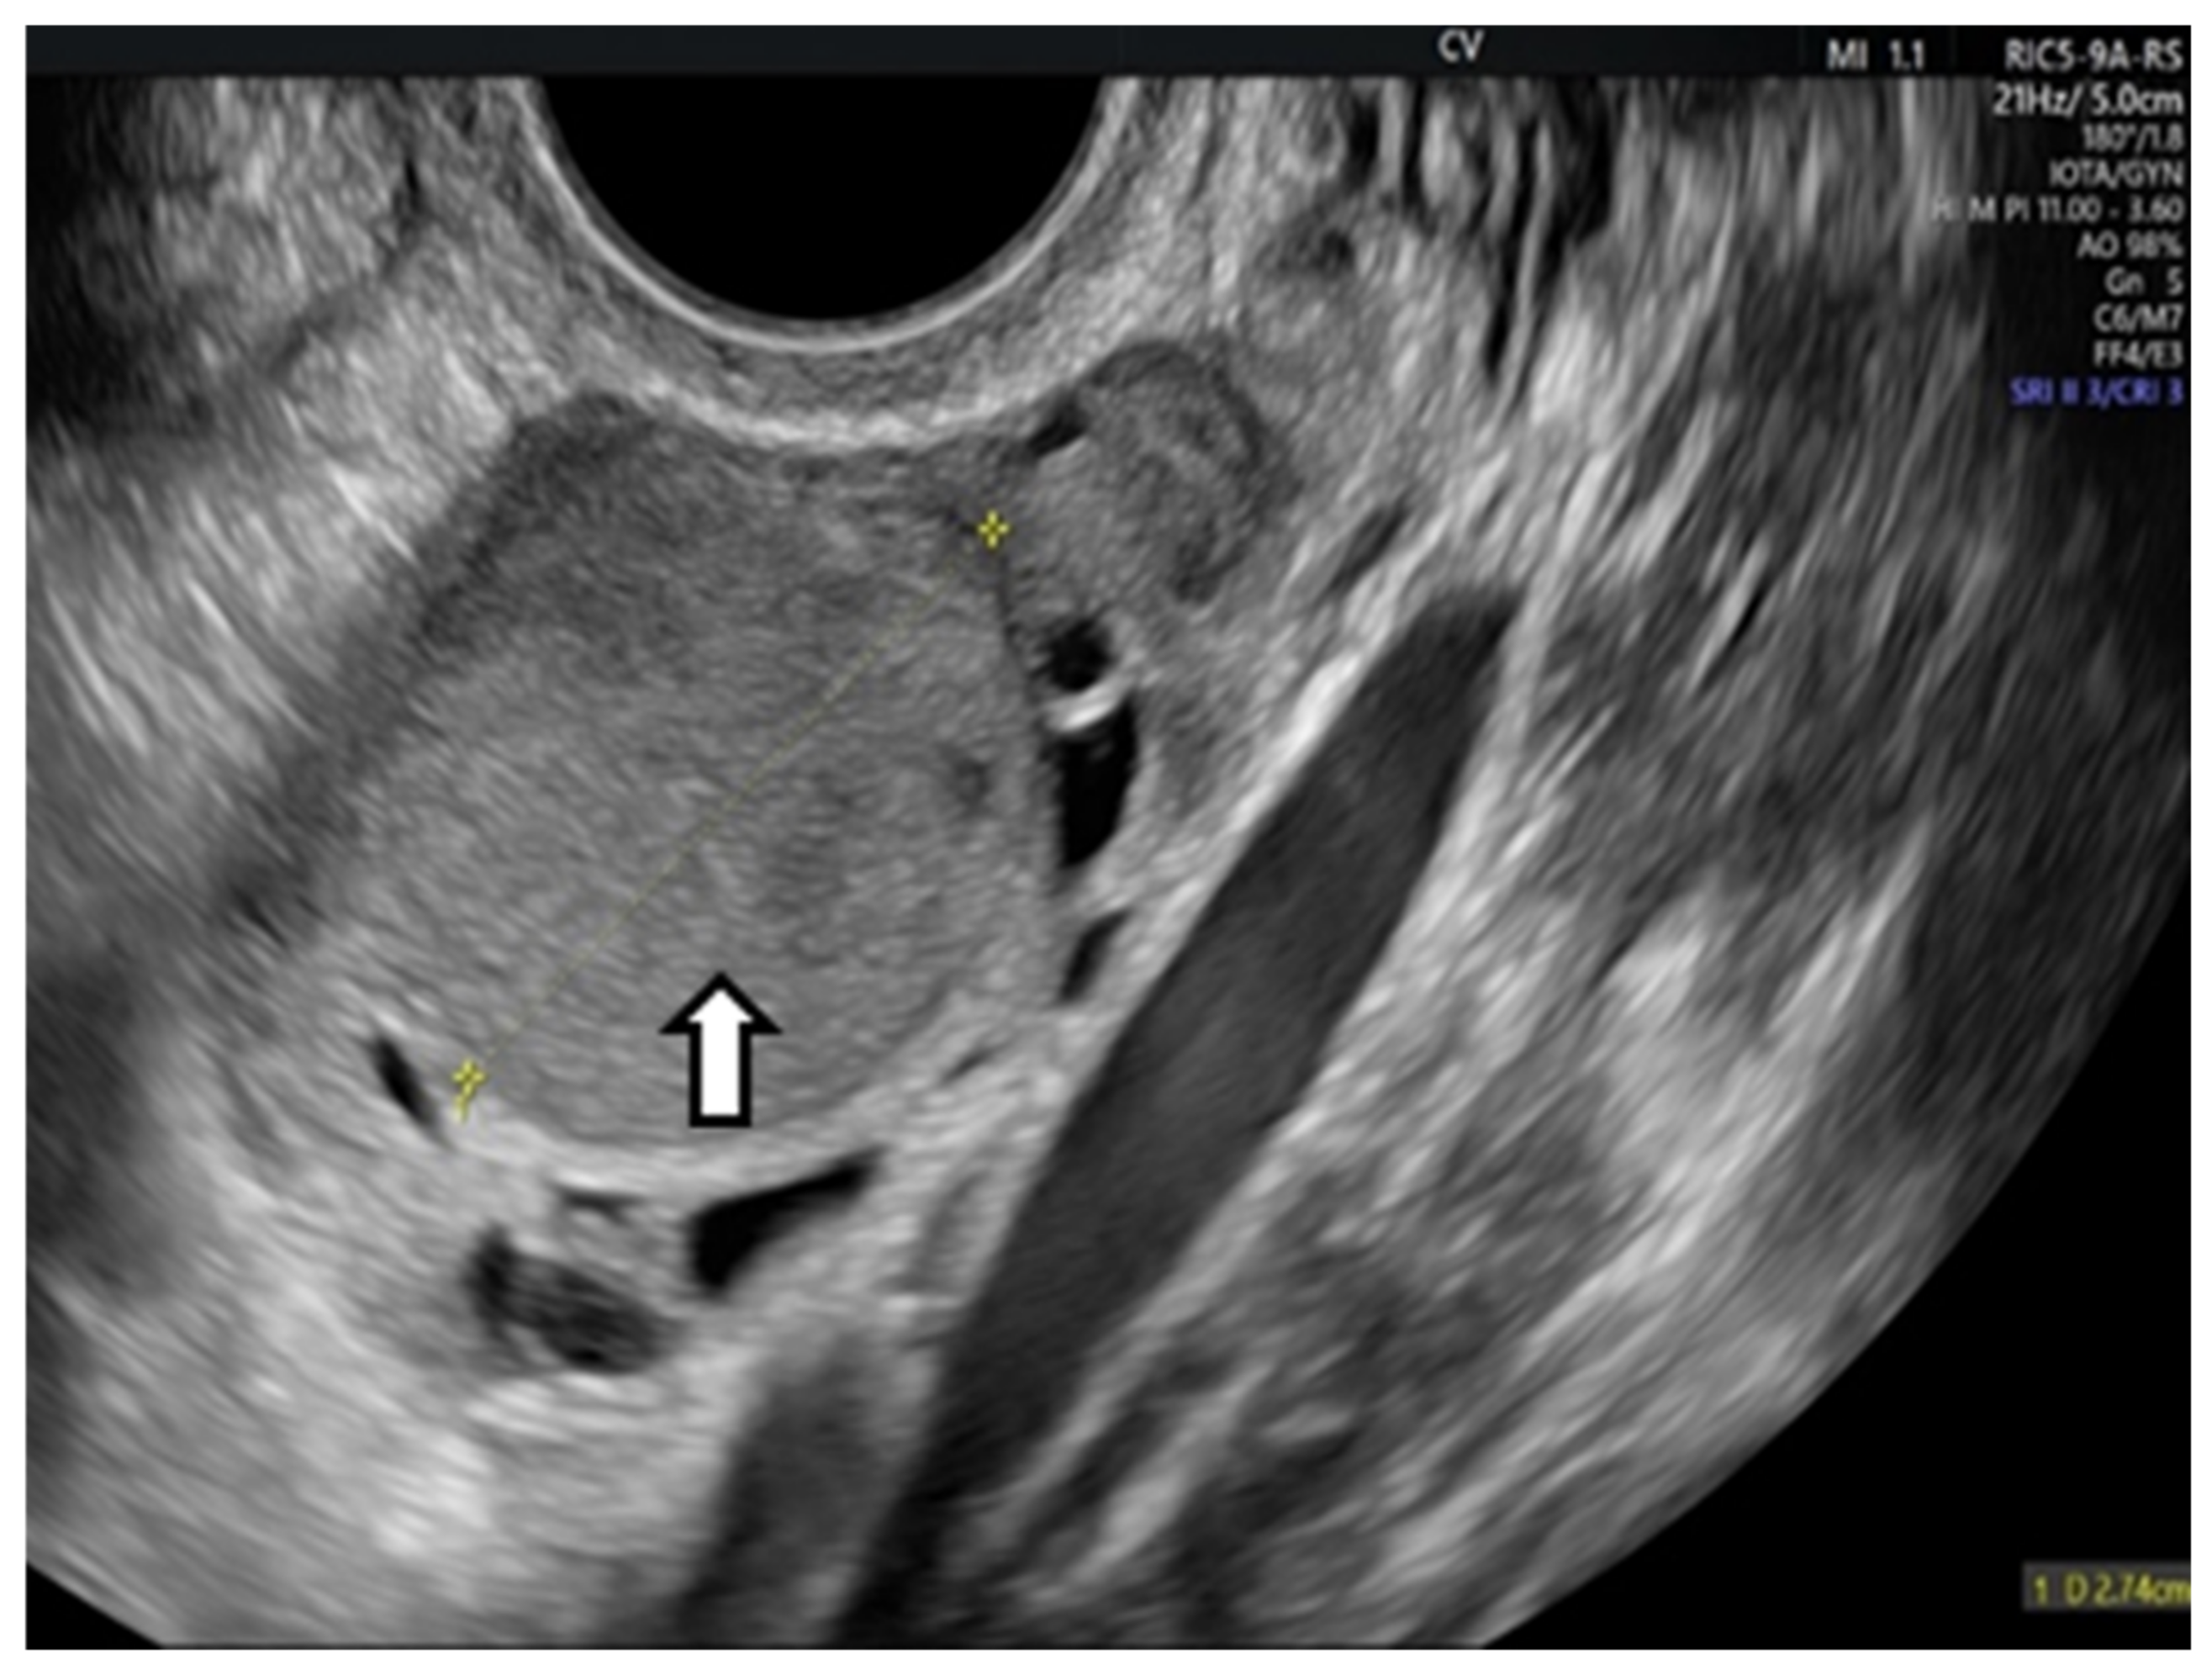

- Cohen Ben-Meir, L.; Mashiach, R.; Eisenberg, V.H. External Validation of the IOTA Classification in Women with Ovarian Masses Suspected to Be Endometrioma. J. Clin. Med. 2021, 10, 2971. [Google Scholar] [CrossRef] [PubMed] [PubMed Central]

- Guerriero, S.; Ajossa, S.; Gerada, M.; Virgilio, B.; Angioni, S.; Melis, G.B. Diagnostic value of transvaginal ’tenderness-guided’ ultrasonography for the prediction of location of deep endometriosis. Hum. Reprod. 2008, 23, 2452–2457. [Google Scholar] [CrossRef]

- Guerriero, S.; Alcazar, J.L.; Ajossa, S.; Pilloni, M.; Melis, G.B. Three-dimensional sonographic characteristics of deep endometriosis. J. Ultrasound Med. 2009, 28, 1061–1066. [Google Scholar] [CrossRef] [PubMed]